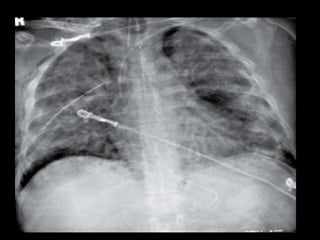

Diseased Lungs Do

Not Fully Collapse,

Despite Tension Pneumothorax

…and

They cannot always

be fully “opened”

Dimensions of a fully

Collapsed Normal Lung